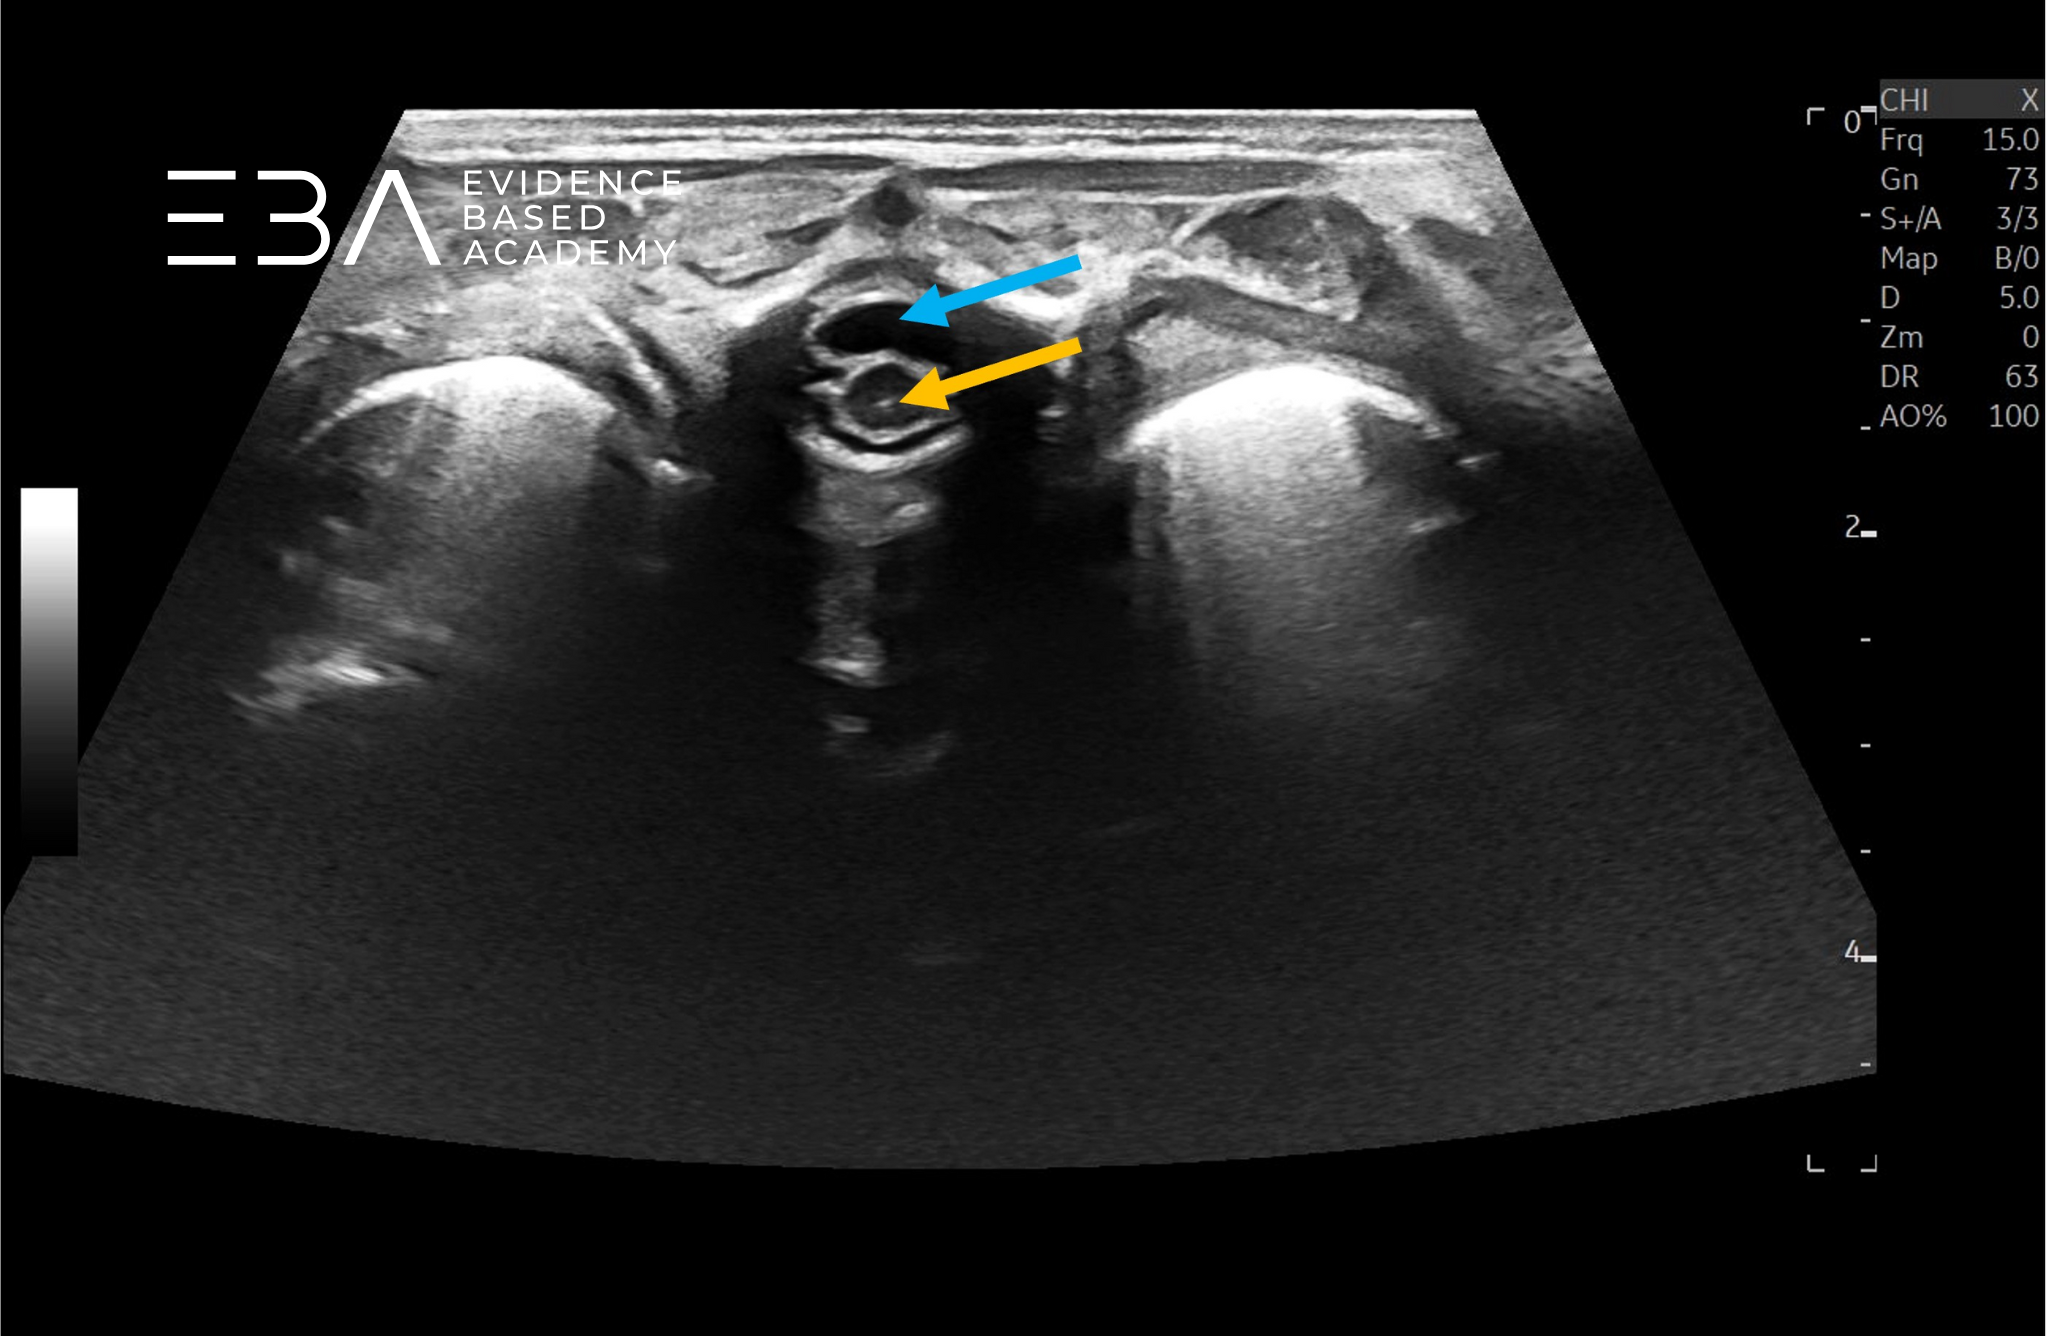

fot. 15

Przekrój poprzeczny kanału kręgowego w odcinku lędźwiowym. Niebieską strzałką zaznaczono przestrzeń podpajęczynówkową, pomarańczową strzałką rdzeń kręgowy.